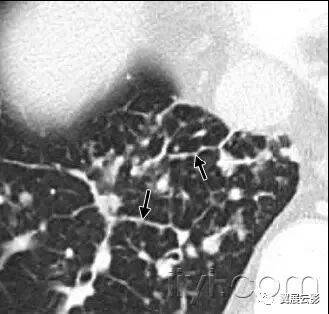

二十五、蜂窝征

病理:蜂窝征代表肺组织的破坏和纤维化,包括大量的囊样含气腔隙和厚纤维壁,是各种肺疾病的晚期改变,已经完全失去了腺泡的解剖结构。囊肿的直径大小从数个毫米到数个厘米,囊壁厚度不一,覆盖以化生的细支气管上皮。

平片和CT:在胸片上,蜂窝征表现为相邻很近的环状阴影,直径主要在3-10mm,壁厚主要在1-3mm,形似蜂窝。这一发现提示肺疾患的终末期。在CT上表现为成簇的囊样含气间隙,其直径大约在3-10mm,偶有大于62.5px的。蜂窝征通常见于胸膜下,具有清晰的壁是其特征,是肺纤维化的CT特征。因为蜂窝征常作为肺纤维化的特异性指标,是常见性间质性肺炎的诊断依据。应当慎用本术语,他可能对病人的治疗产生直接影响。